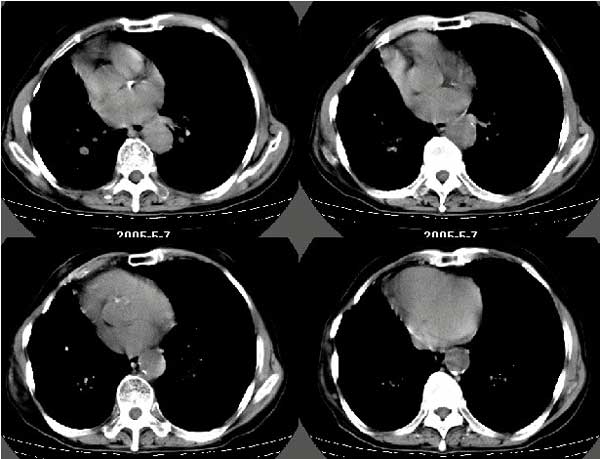

以下是引用扬仪在2005-5-12 20:46:40的发言:[br]右肺呈术后改变;双侧肺野散在分布斑片状、点状高密度病灶,(似可见“树芽征”);左上尖后段见斑团状高密度病灶(2个层面?),边缘毛糙,段性分布,与斜裂相邻,临近胸膜粘连;增强示病灶边缘强化,内呈水样密度;心影、纵隔右移,内可见4r淋巴结肿大。[br]意见:1、双肺继发性肺结核,左上为干酪病灶;[br] 2、矽肺合并感染;[br] 3、建议抗痨+抗炎。 [br]愚人之见,请高人指教!